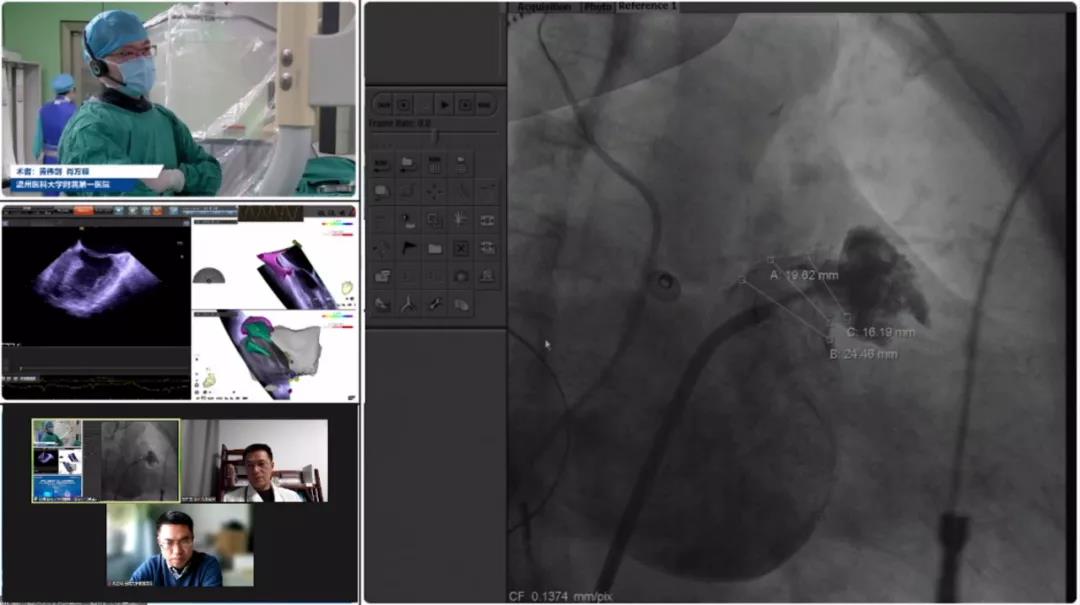

Case 4

荆州医科大学从属第一医院黄伟剑、肖方毅教授团队

患者女性,73岁,因体检发现心房抖动8月余入院,患持续性房颤、高血压及肝硬化史,CHA2DS2-VASC评分3分,HAS-BLED评分2分,拟在ICE疏导下行LAmbre?左心耳封堵术;颊咴诰致橄滦凶笮亩舛率,左心耳丈量锚定区约为16mm,封堵区约为24mm,选择LAmbre?型号为1832的幼伞大盘封堵器进行植入。封堵器安全搁置后,ICE下多角度观察未影响周围组织、未见心包积液、未见残存分流。LAmbre?怪异的锚定机造能确保左心耳封堵器不变牢固,牵拉测试极度不变,切合COST准则,随后开释封堵器。